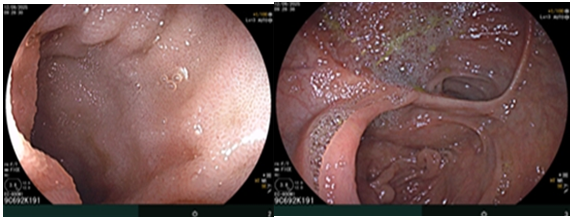

Hình 1. Hình ảnh sỏi đường mật tạo ổ áp xe gan - đường mật gan trái (vòng tròn màu đỏ). Giãn nhẹ đường mật trong gan hai bên. Dày thành nhẹ ngã ba đường mật trên phim chụp cắt lớp vi tính.

Đánh giá tổn thương trên phim chụp cộng hưởng từ: Nhu mô hạ phân thuỳ IV có ổ tổn thương dạng dịch, kích thước 38x52mm, trong có vài sỏi, sỏi lớn nhất kích thước ~27x37mm, có thông với nhánh đường mật gan phải lân cận, ngấm thuốc viền sau tiêm, chèn ép ngã ba đường mật, gây giãn đường mật trong gan hai bên

Hình 2. Hình ảnh giãn khu trú đường mật gan trái, tạo cấu trúc dạng nang và sỏi đường mật bên trong( vòng tròn đỏ), chèn ép kèm giãn đường mật trong gan hai bên trên phim chụp MRI